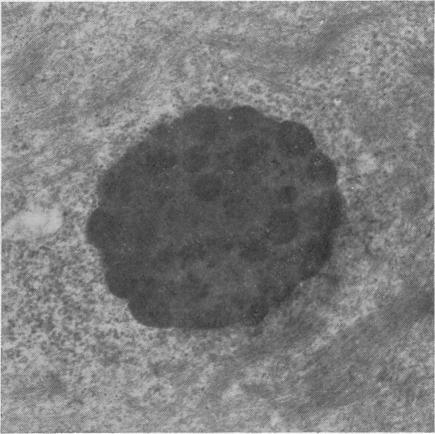

The morphology of the keratinizing epithelia in the mouth is reviwed in the light of recent knowledge. There appears to be a spectrum of degrees of keratinization rather than distinct types, and a degree of keratinization is reflected in the degree of packing and orientation of tonofilaments. The role of keratohyaline and other granules in the process is discussed and it is suggested that modification of the cell membrane is an important part of keratinization. Although the potential of the various areas in the mucosa is genetically determined and appears early in fetal life, the connective tissue exerts an influence on the extent of keratinization of the surface in a manner which is not understood.

根据最新知识,对口腔中角化上皮的形态进行了综述。角化程度似乎存在一个连续谱,而非不同类型,角蛋白丝的聚集和排列程度反映了角化程度。文中讨论了透明角质颗粒及其他颗粒在此过程中的作用,并提出细胞膜的修饰是角化的重要组成部分。尽管黏膜各区域的潜能由基因决定且在胎儿期早期就已显现,但结缔组织以一种尚不清楚的方式影响着表面的角化程度。